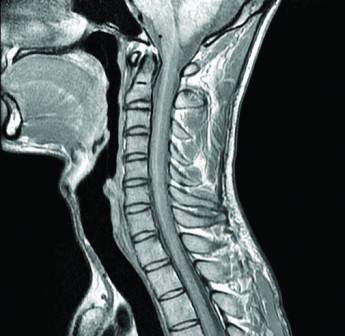

МРТ шейного отдела позвоночника

– что показывает

С возрастом увеличивается вероятность костных разрастаний, остеохондроза, унковертебральных артрозов, являющихся причиной необратимых мозговых расстройств. Грамотная расшифровка МРТ шейного отдела позвоночника (ШОП) позволяет обнаружить состояния с нарушением транспорта крови по мозговым артериям или компрессией спинномозговых корешков, приводящей к болям затылке, верхних конечностях. Пациенты с вертебробазилярной недостаточностью нередко утрачивают сознание из-за недостатка внутричерепного кровоснабжения. По анатомическим данным 20-30% крови к мозговым тканям доставляется через позвоночные артерии (правую и левую). При ущемлении этих сосудов смещенными позвонками, опухолями возникает хроническая гипоксия с необратимыми изменениями нейронов мозга.

Как проводят МРТ шейного отдела позвоночника – основные особенности

Магистральные сосуды шеи повреждаются не только при патологии позвоночных сегментов, но и за счет атеросклероза, закупорки кровяными сгустками, попадающими из расширенных варикозных вен. Множественность патологии определяет особенности процедуры мрт шейного отдела, краниовертебрального перехода.

Описание показаний к мрт шейного отдела позвоночника:

- Выпадение межпозвонкового диска (для выявления грыжи);

- Сужение спинномозгового прохода (стеноз);

- Нарушение спинальной микроциркуляции;

- Опухоли;

- Демиелинизирующие состояния (рассеянный энцефаломиелит, склероз);

- Изучение мягкотканых структур после травматического воздействия, компрессионного перелома;

- Аномалии строения;

- Оценка толщины структуры кости (остеопороз), выявленной на снимке;

- Определение фактора затруднения кровоснабжения в области шеи.

Преимущество магнитно-резонансной ангиографии шейного отдела позвоночника – высокая вероятность выявления повреждения нервных оболочек, визуализация повреждений спинного мозга.

В большинстве центров диагностика на МРТ шейного отдела позвоночника осуществляется с использованием классических GRE, T1 и T2 режимов. Подхода достаточно для обнаружения большинства изменений мягких тканей.

Некоторые частрые клиники предлагают дополнительное решение – параллельная визуализация (осевая GRE), перенимая передовой опыт зарубежных исследователей. Такое сканирование позволяет изучать более мелкие анатомические детали исследуемой зоны.

Из-за небольших размеров шеи при сканировании на стандартных режимах не визуализируются патологические очаги менее 2 мм диаметром. Для устранения недостатка необходимы технологии повышения контрастности и чувствительности. Для этих целей европейские врачи лучевой диагностики используют методику «GM/WM контрастирование», позволяющую сочетать одновременно несколько режимов для улучшения качества томограмм шейного отдела позвоночника.